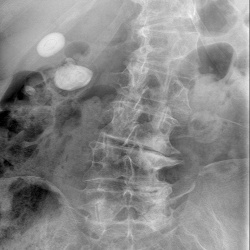

Пациентка 62г. поступает в приёмный покой больнцы в связи с болями в животе, подъёмы температуры до 38 градусов.Выставлялась болень Крона.Выполнен обзорный снимок брюшной полости.